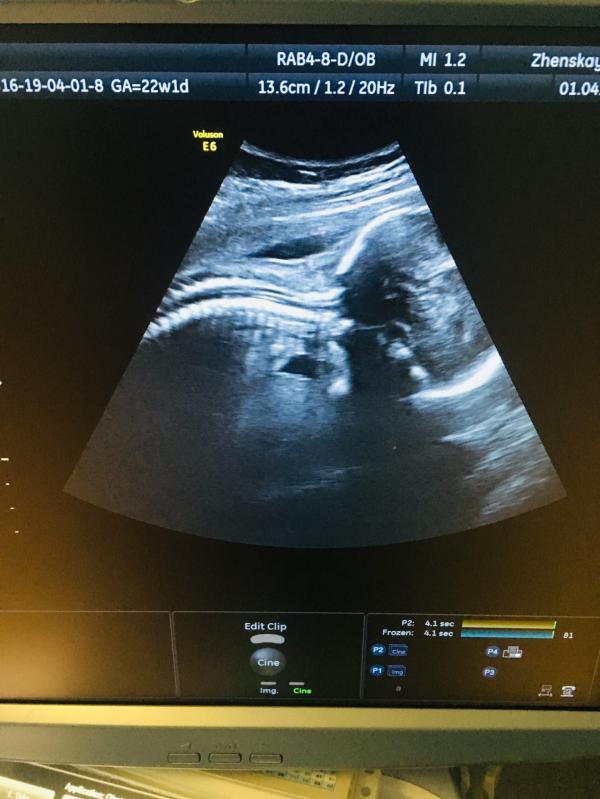

Всем доброе утро,вчера ходила на Узи,жду вторую доченьку😍❤️🎆